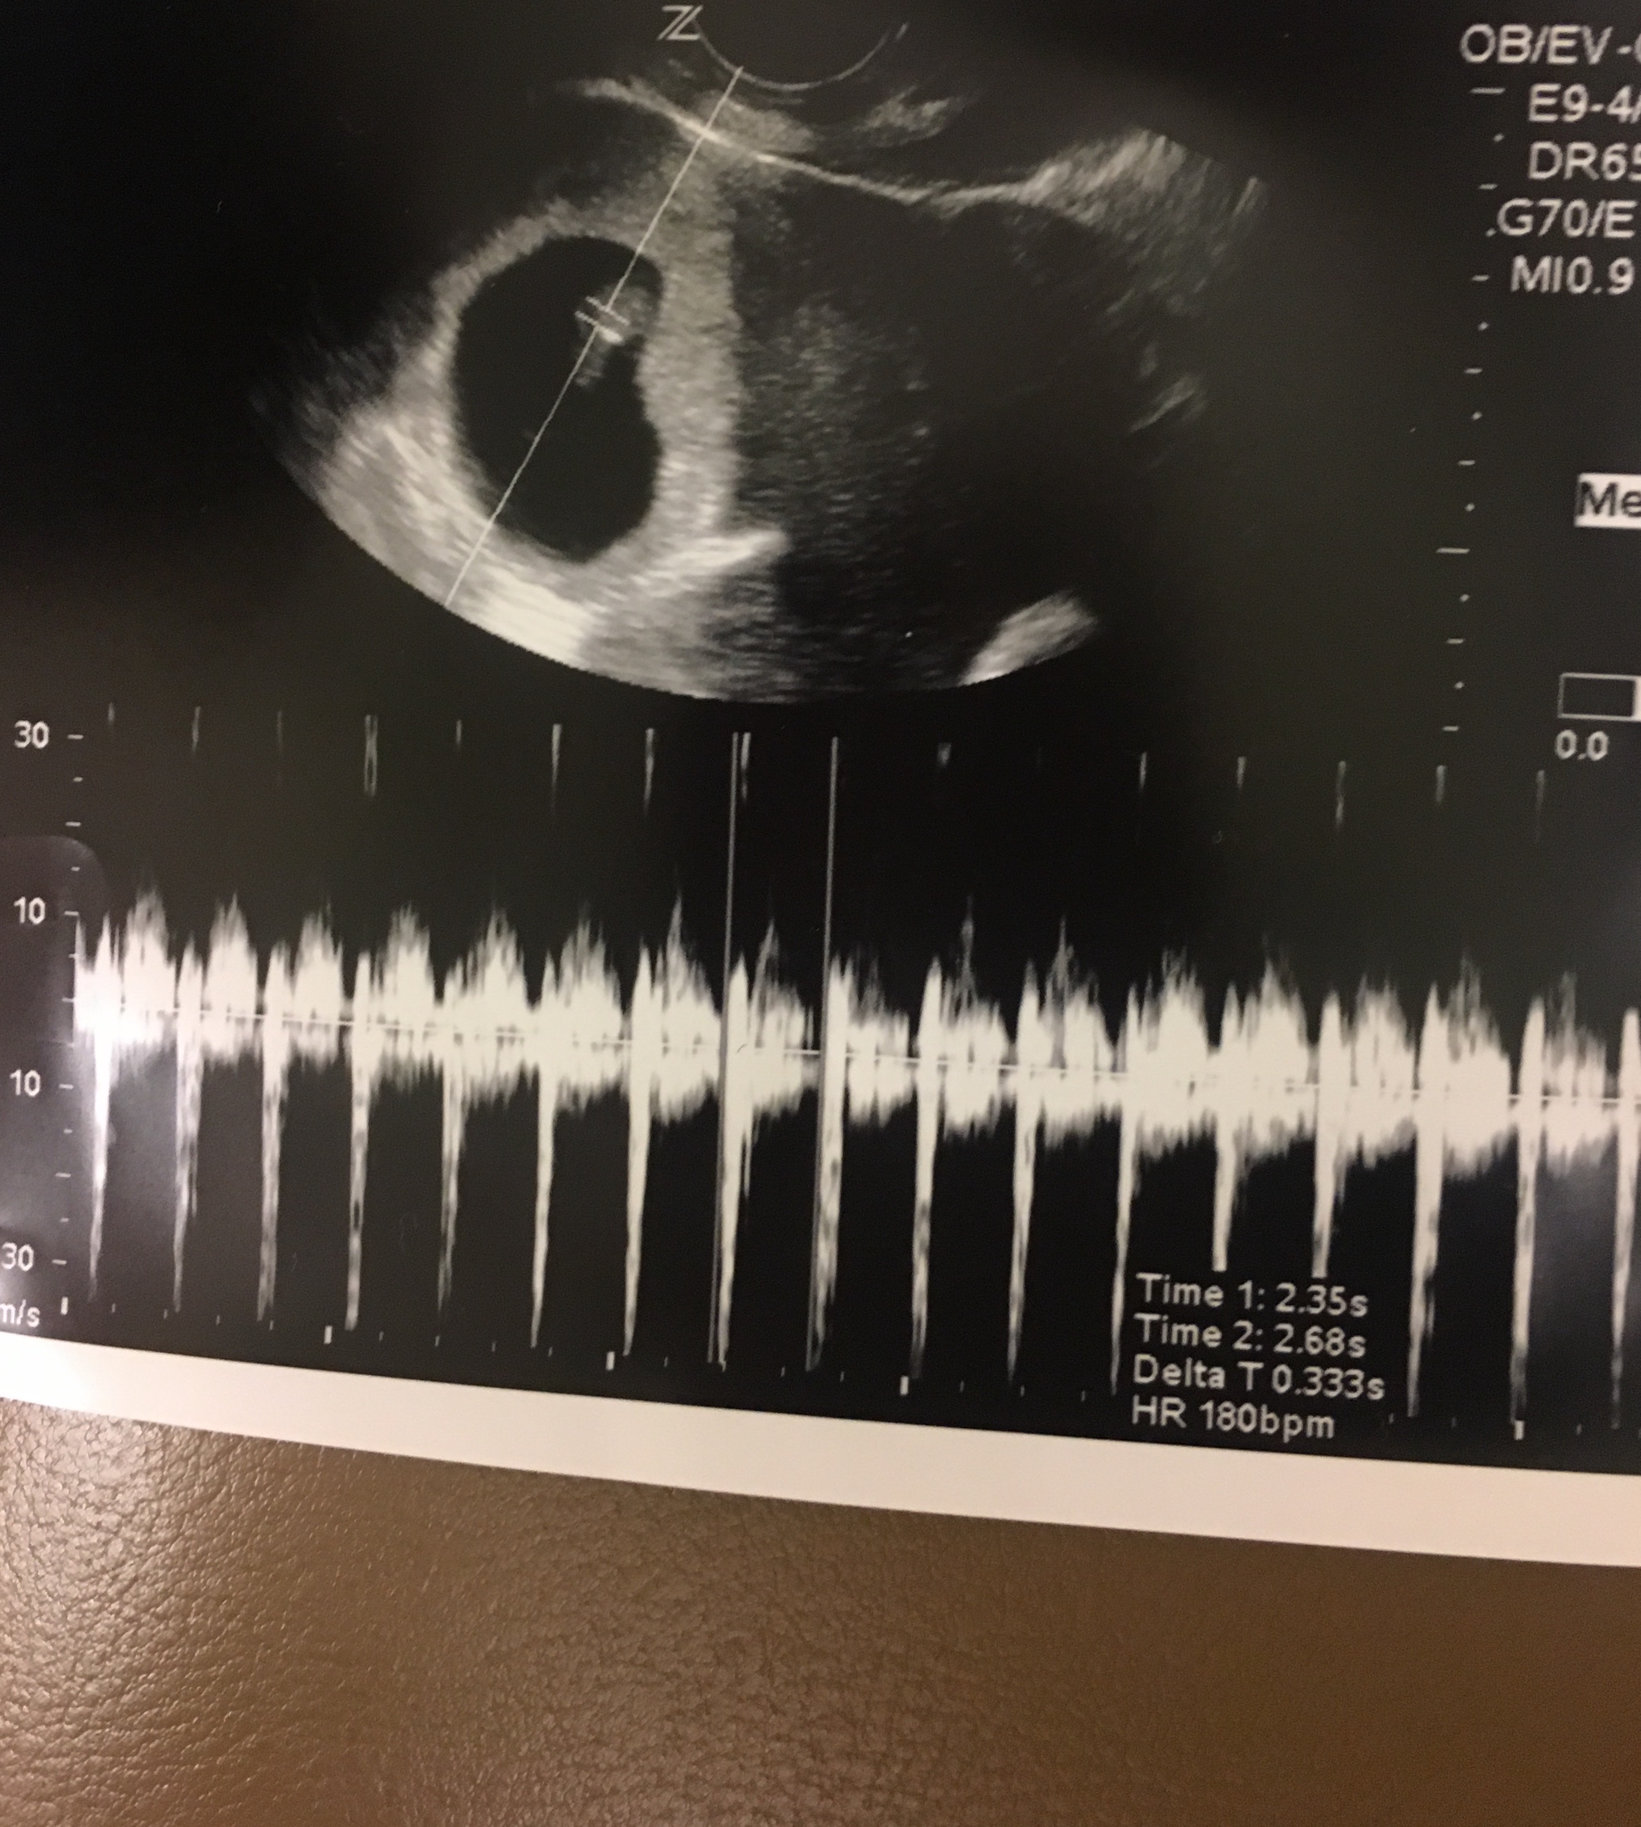

Had another ultrasound Sunday at the ER I was 9w2d and I had pain and bleeding. They found a hemorrhage but baby was doing good HR was 170 and the baby even looks like they’re smiling!